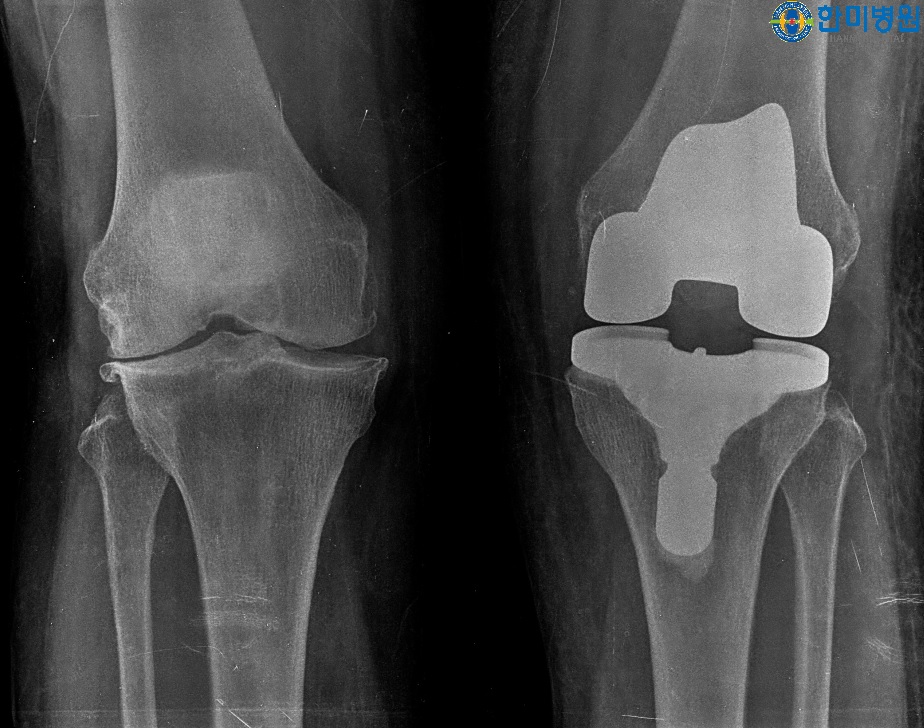

[무릎인공관절 수술 후 사진]

[무릎인공관절 수술 전 사진]

환 자 명 : 김**님

나 이 : 64세

수 술 일 : 2017년 01월 오른쪽 무릎인공관절 수술

2017년 02월 왼쪽 무릎인공관절 수술

수술 병원 : 한미병원

방 문 일 : 2018년 05월

환우분 상태 및 안내 : 자고 일어나거나, 걸을 때 무릎에서 소리가 들린다고 하심 수술 전 완전히 걸을 수 없는 상태에서 지금은 매일 40분씩 걷기 운동하심, 수술 부위 굴곡 140° 정도 수월하시고 양반다리도 가능하심, 운동을 안할 경우 확실히 무릎의 움직임이 다르다고 하시면서 스스로 근력강화의 중요성을 인식하고 계심